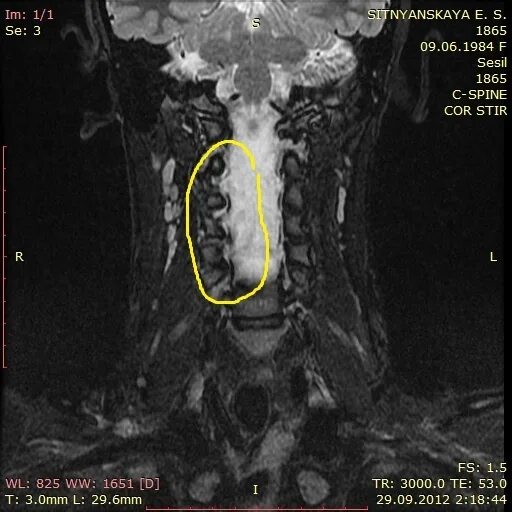

Дегенерация межпозвонкового диска по pfirrmann